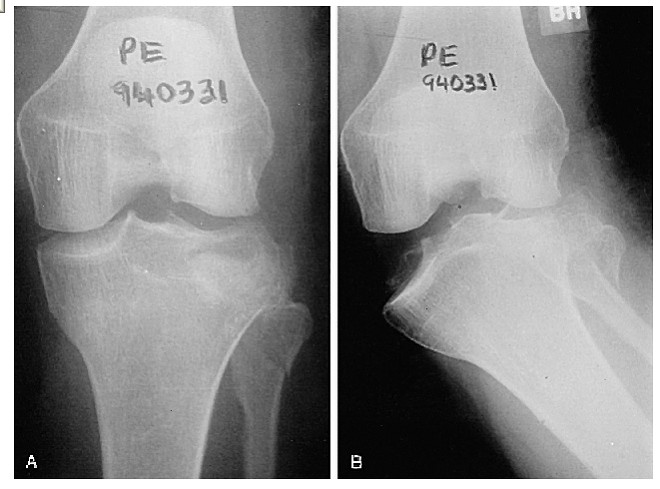

These fractures can be quite subtle and should always be considered when assessing acute knee injuries. Usually the common patterns of tibial plateau fractures are identified on plain films (AP, LAT, OBLIQUES).

This film shows a lateral tibial plateau fracture with depression and comminution. There is a less obvious extension of the fracture through the medial tibial plateau and in fact the knee is no longer connected to the shin! |